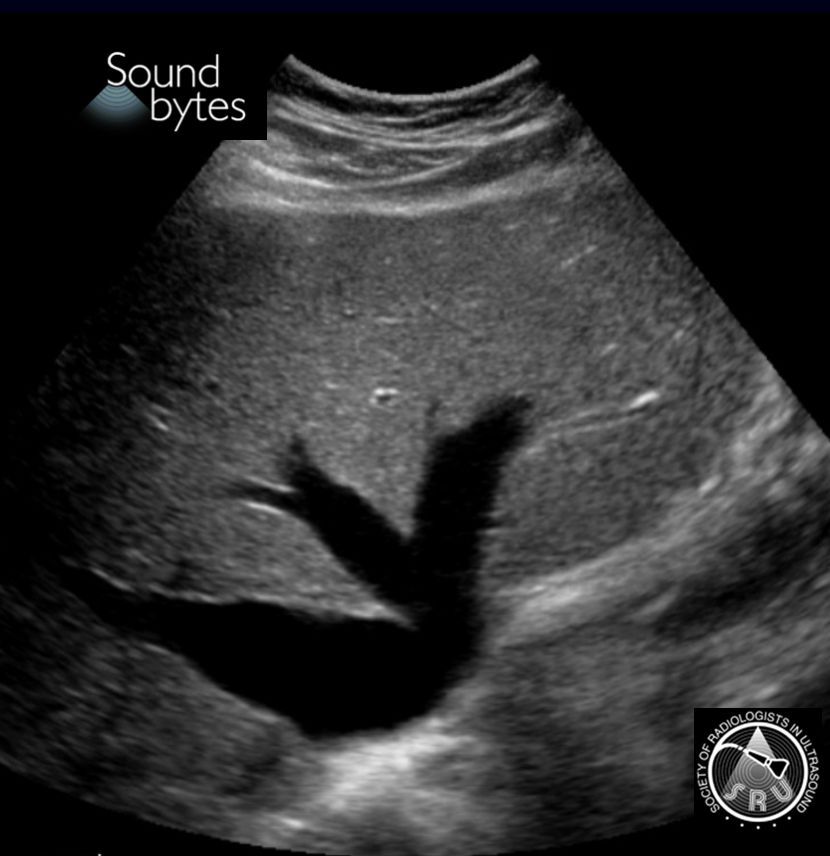

Dx: Cardiogenic congestive hepatopathy.

Findings: Gallbladder wall edema 2/2 liver congestion, dilated hepatic veins, and CXR showing cardiomegaly.

Case courtesy of Dr. Eugenio Zalaquett, Red de Salud UC-Christus, Santiago, Chile